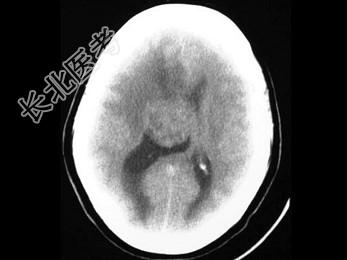

- 单项选择题女,31岁, 癫痫发作,头痛, 头晕,结合图像, 最可能的诊断是 ( )

A、脑膜瘤

B、脑囊肿

C、星形细胞瘤

D、脑膜炎

E、室管膜瘤